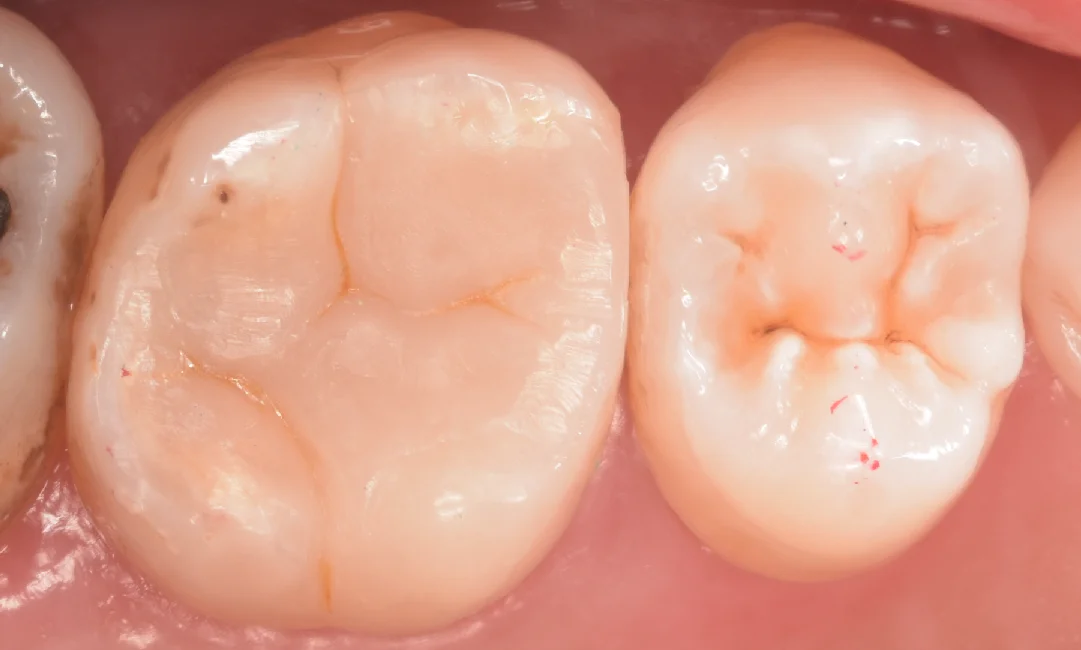

そして詰め終わったのがこちらになります。

ある程度違和感なくしっかりと詰められたかと思います。